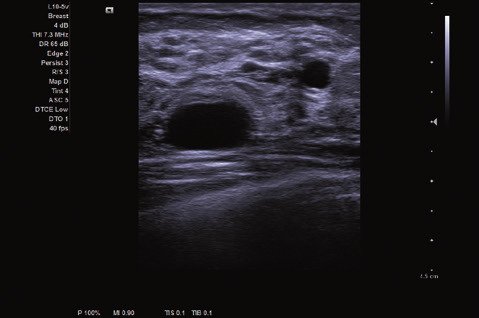

Das ACUSON NX2 Ultraschallsystem besitzt eine zukunftsfähige digitale Plattform mit nahezu unerreichter Bildqualität und sorgt für effiziente und zuverlässige Diagnosedaten. Die Vielseitigkeit des Ultraschallsystems wird mit einem großen kompatiblen Portfolio an Schallköpfen gedeckt, und so ist für jeden Anwendungsbereich etwas dabei. Die Bedienkonsole ist intuitiv aufgebaut und optimiert und erlaubt bis zu vier nach vorne gerichteten Schallkopfanschlüssen für eine enorme Effizienz und schnellen Workflow. So lassen sich bei der fetalen Bildgebung außergewöhnlich detailgetreue Darstellungen des Fetus im Gesicht zeigen oder durch die herausragende Farbdopplersensitivität bei der Darstellung der kleinen Gefäße des zystischen Schilddrüsenknotens kleinste Details erkennen. Weiterhin besticht das NX2 mit einfacher Aufrüstbarkeit bei wachsenden Anforderungen für Ihre zukünftigen Anwendungen und kompatible skalierbare Schallköpfe verringern ihren Kapitaleinsatz um bis zu 31 %.